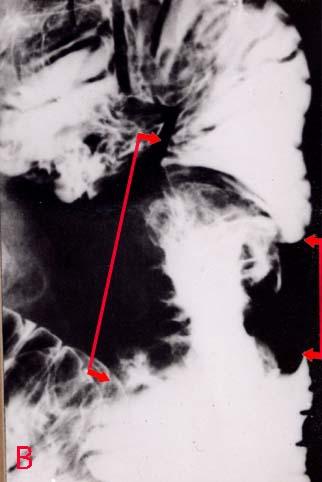

便血,术前诊断为肺癌的转移性小肠肿瘤切除病例(52岁,男性)X光片   小肠造影X光片,病变部分充实,病变(箭头)在空肠上部,伴有两侧性狭窄和阴影缺损。病变界限比较明显,为肿瘤形态,呈与原发性进行性小肠癌极近似的所见。但是,阴影缺损部分的边缘有所谓的海螺外壳、scalloped margin (大海螺的外壳状、波浪状)所见。

疾病(病理主体)的分类转移性肿瘤/

部位(按器官分)小肠/空肠

检查方法X线

肿瘤最大直径40以上